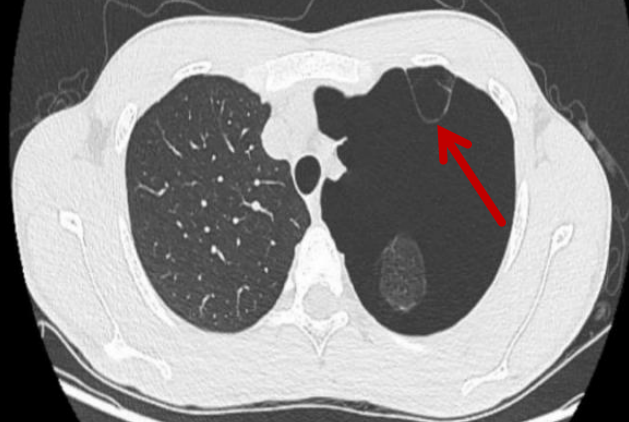

20 岁的文同学(化名)是名在校大学生,因「左侧胸痛 1 周」来到我院就诊。检查后胸部 CT 提示:左侧大量气胸(左肺受压约 80%),合并有肺大疱。

「简单说,就是肺上的 『小气泡』 破裂后导致气胸,空气跑到胸腔里把肺挤扁了。」起初经保守治疗,效果并未达到预期。